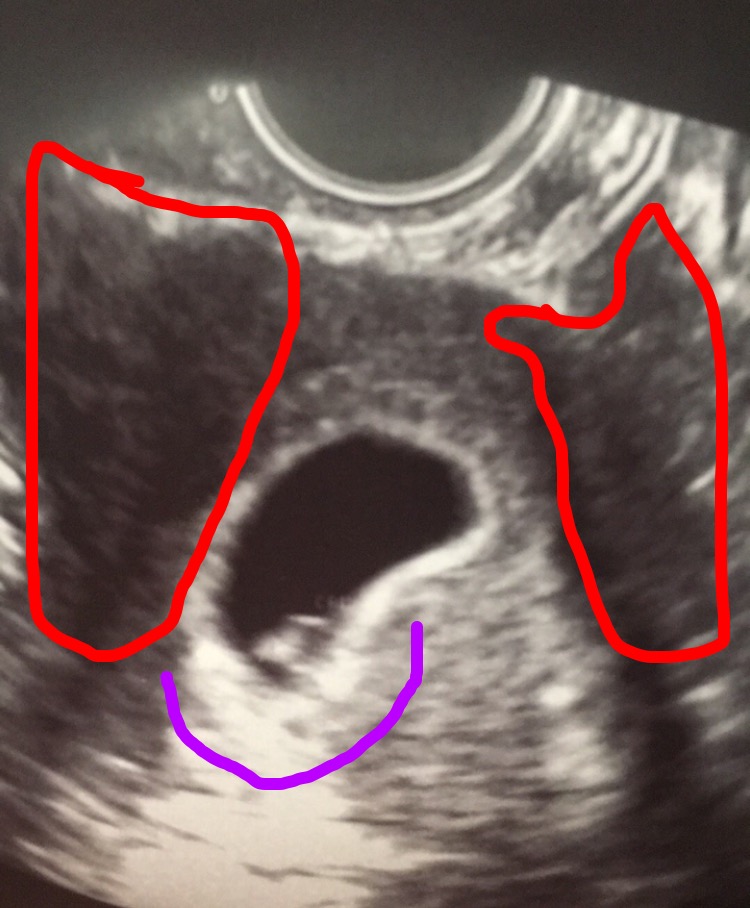

So here is my 6w 2d ultrasound. I Would love a ramzi. Dr said placenta is attached to the left (purple)